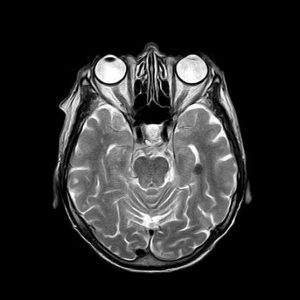

Para cada técnica de imágenes médicas, hay algoritmos especializados, ya que las características de las imágenes son diferentes, y su interpretación también. Por ejemplo, las imágenes de tomografía axial computarizada (TAC) pueden parecerse a las imágenes de resonancia magnética, sin embargo, la información que contienen es muy diferente, como se muestra a continuación.

Imágenes de TAC: se generan empleando rayos x y las formas e intensidades que se observan están relacionadas con la morfología y propiedades físicas de las estructuras anatómicas.

Imágenes de Resonancia: se crean a partir de campos magnéticos y contienen información relacionada con la actividad metabólica y el funcionamiento de los órganos y tejidos.

Izquierda: imagen de resonancia magnética del cerebro. Derecha, TAC del cerebro